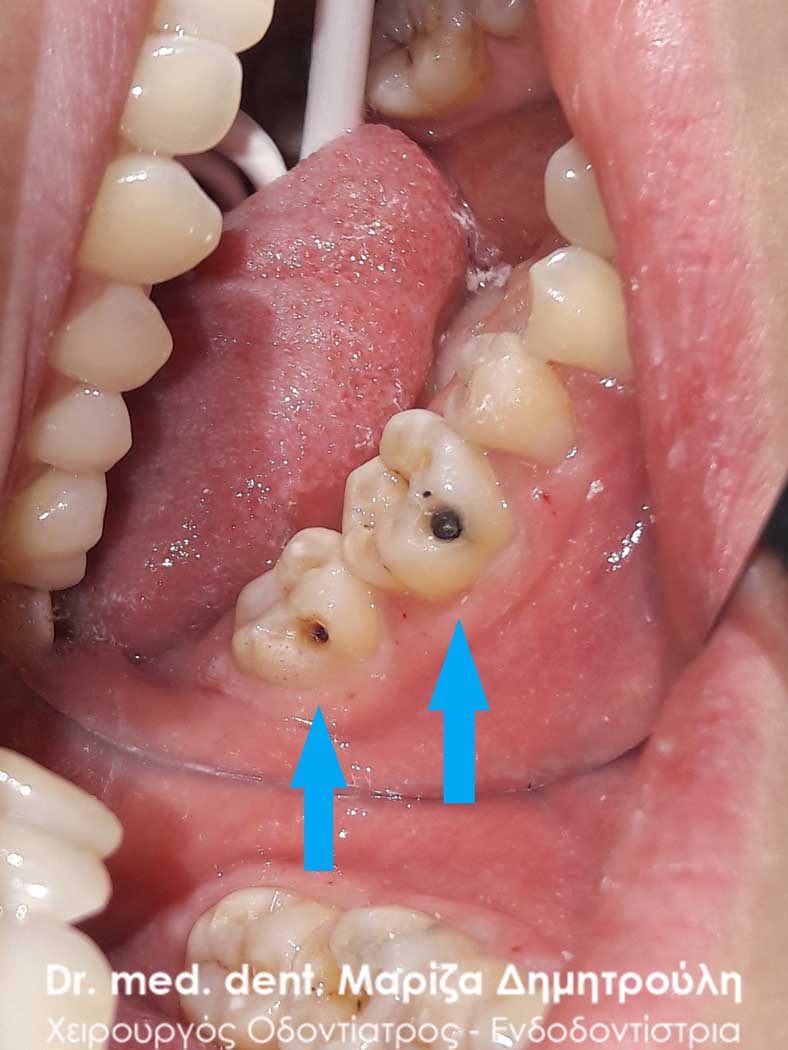

Στο παρόν περιστατικό απουσιάζει η αρχική εικόνα των δύο δοντιών πριν αρχίσει ο εκτροχισμός τους. Διαθέσιμες είναι μόνο η ενδιάμεση εικόνα που παρουσιάζει το εύρος του οδοντικού ελλείμματος στα δύο γομφίους της αριστερής πλευράς της άνω γνάθου και η τελική εικόνα αποκατάστασης των δύο δοντιών.

Η ασθενής αισθανόταν τις τελευταίες μέρες έναν ήπιο πόνο κατά τη μάσηση τροφών. Μετά την κλινική εξέταση του στόματος διαπιστώθηκε η ύπαρξη τερηδονικών κοιλοτήτων στους δύο άνω αριστερούς γομφίους. Αποφασίστηκε με τη συναίνεση της ασθενούς η αντικατάσταση των σφραγισμάτων. Στον πρώτο γομφίο διορθώθηκε μόνο η μισή έκταση του παλιού σφραγίσματος, καθώς κρίθηκε οτι δεν ήταν απαραίτητη η αφαίρεση ολόκληρου του παλιού σφραγίσματος.